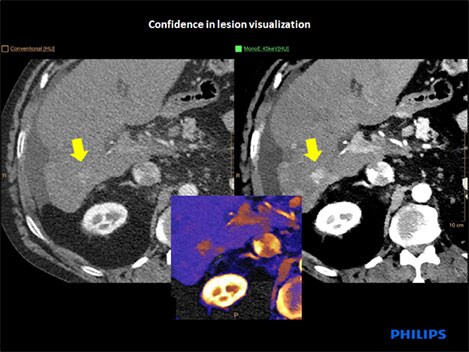

Case study: lesion visualization

This scan is a follow-up after ablation of hepatocellular carcinoma to see the effect of treatment. This patient also has a history of liver cirrhosis. On the conventional CT image (top left) there appears to be a poorly defined area of enhancement (yellow arrow). Changing to monoenergetic view at low energy (top right) boosts the iodine signal, showing that the area of the lesion is metabolically active. An overlap image of the iodine signal in color (center) clearly shows the de-novo hepatocellular carcinoma.